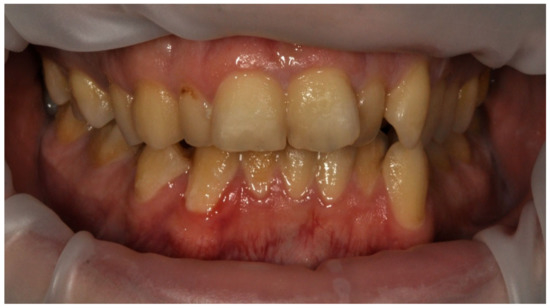

The mean API score among the subjects was 63.47% (SD = 22.78) and ranged between 22 and 100%. The mean value of the index for the control group was 68.75% (SD 21.46) and ranged from 19 to 100%. The p > 0.05, therefore the study and control groups did not differ significantly from the API value. The median value of the API index for the study group was 65 and 68.5 for the control group. Table 3 and Figure 1 present the API score and the API score pictured according to interpretation values. Figure 2, Figure 3 and Figure 4 show the clinical situation of the participants. The API values did not have a normal distribution in the analyzed groups (p < 0.05 from the Shapiro–Wilk test), so the analysis was carried out using the Mann–Whitney test.

Figure 4. Man, 42 y.o. API = 100%. The patient refused to use professional oral hygiene products and used soap to brush his teeth. Dental plaque deposits. Dental Biofilm-induced Gingivitis.

Ijerph 20 04792 g004